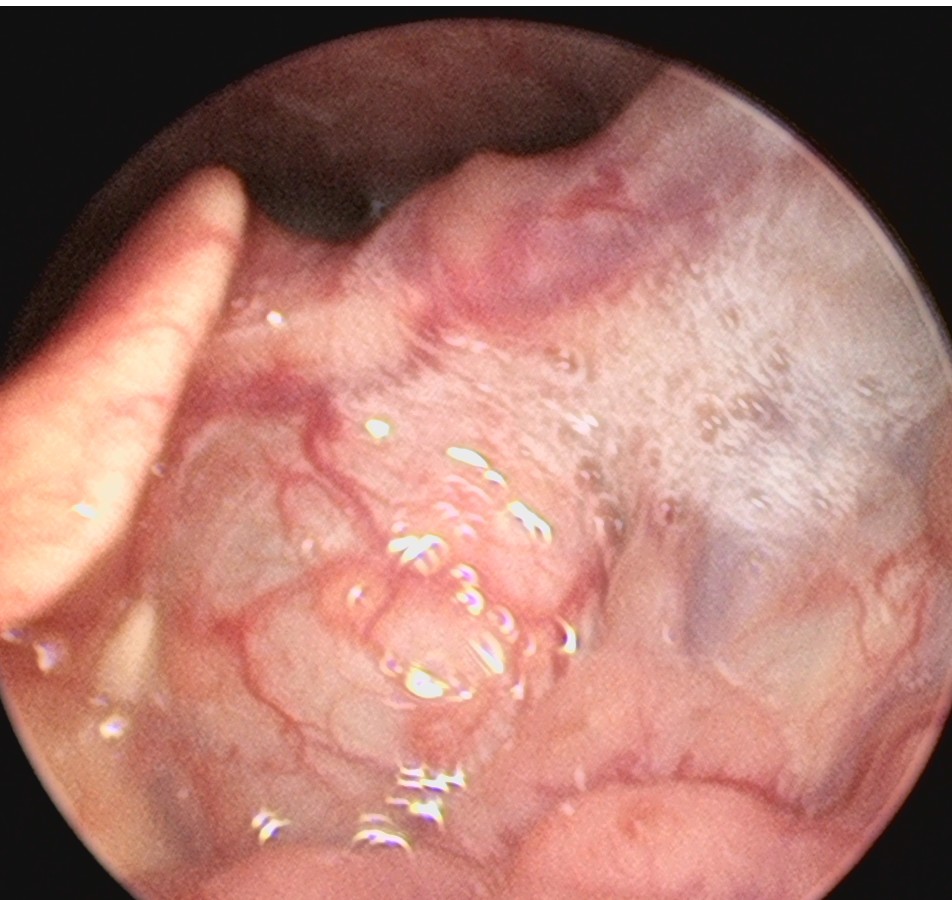

来自广东梅州的管叔,最近发现颈部肿物2周,不痒,不痛,自觉问题不大。但是肿物越来越大了,在家人的劝说下来到佛山复星禅诚医院耳鼻喉做了检查发现是颈部的先天性囊肿。

这个年龄阶段发现颈部的先天性囊肿是比较少见的,一般这种病没有多少的不舒服,但需要做手术切除才可以根治。一般手术早点做效果要好一些,如果囊肿长的比较大了,手术的范围也会相应的扩大,术后恢复就可能会慢一些,手术的风险也会相应的增大。